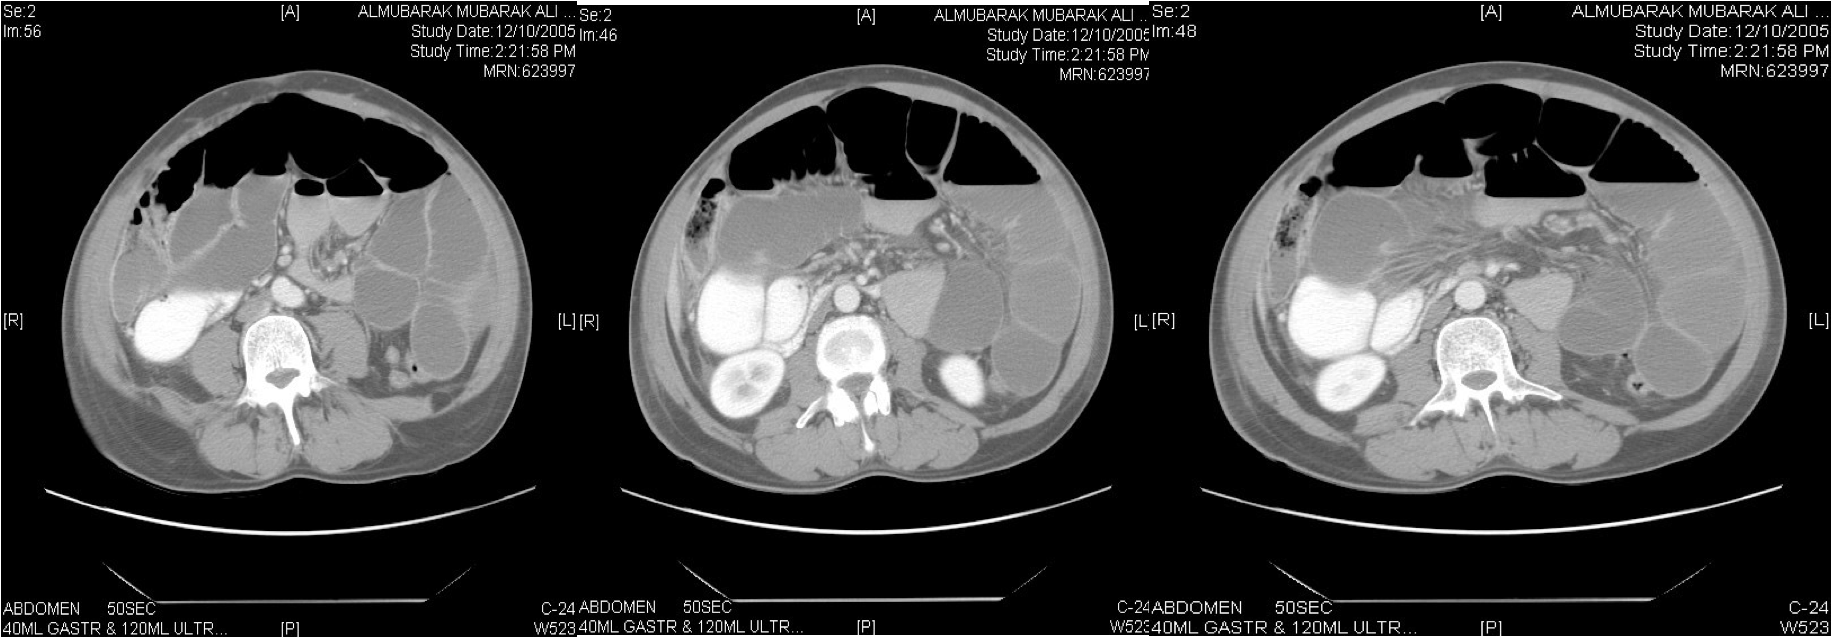

Computed tomography may also show any responsible tumour or inflammatory mass